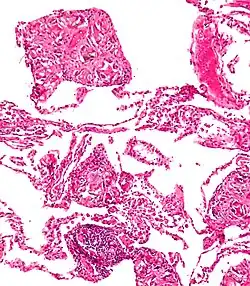

Foreign bodies in the peritoneum eventually become contained in a foreign body granuloma. In the extremely rare case of retained ectopic pregnancy, this forms a lithopedion, which involves the fetus being too large to be reabsorbed, and is calcified[13] as a means of shielding the surrounding tissue from infection.